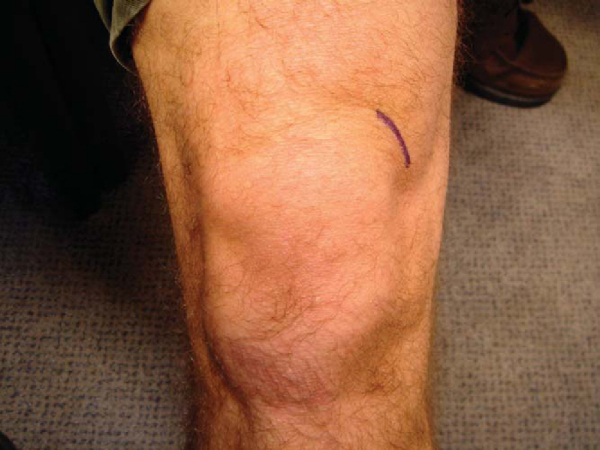

An incision is made in Langer’s lines at the medial knee slightly anterior and superior to the medial femoral epicondyle (

Fig. 68-8

). Dissection is carried down in line with the vastus medialis muscle to the level of the condyle. It is important to visualize the bone at this stage for protection of the soft tissues and for accurate placement of the PCL guide. In addition, good visualization allows easy identification of the tunnel when you are ready to perform femoral tunnel fixation. The guide is placed with arthroscopic assistance at the 1-o’clock position (on the right knee) or the 11-o’clock position (on the left knee) and 8 mm deep (away from the articular surface) (

Fig. 68-9

). The guide pin is drilled from outside in by use of the PCL guide, with the ideal placement in the medial femoral notch confirmed arthroscopically. The starting point of the guide pin must be proximal (farther from subchondral bone) enough to avoid subchondral collapse, insufficiency fractures, or avascular necrosis of the condyle from drilling of the femoral tunnel.[1] The tunnel is then drilled over the guide wire, and the edges are débrided to facilitate graft passage at a later stage. A looped smooth 18-gauge wire is placed retrograde through the tunnel into the joint and used to pass the autograft from the back of the knee into the joint and femoral tunnel at a later stage.